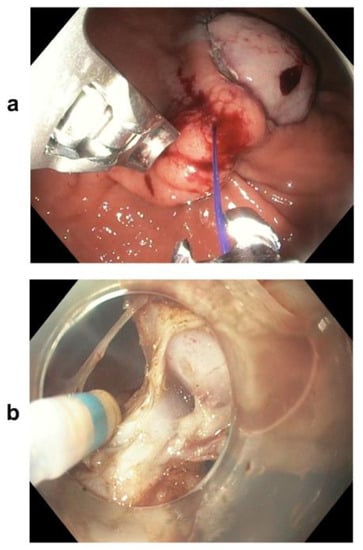

2.2. Resection Techniques

- The hybrid technique combining endoscopic resection and endoluminal suturing appears to be a potential alternative for selected gastric GISTs with a large size and a high MP connection grade (type > I), with advantages over ESD.